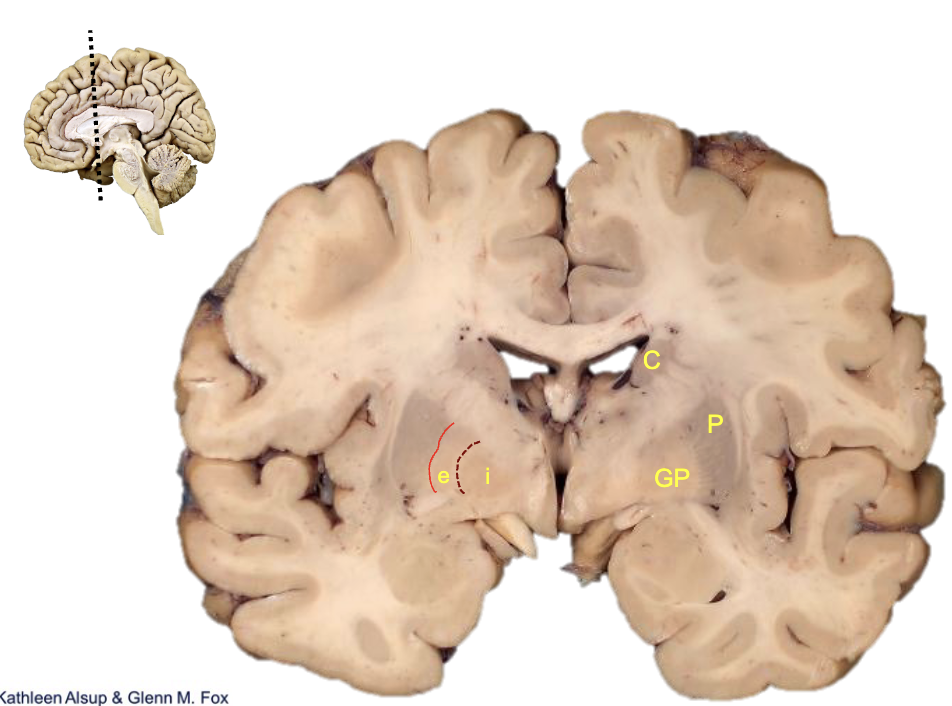

<p><strong>what is c?</strong></p>

caudate

<p><strong>what is p?</strong></p>

putamen

<p><strong>what is gp?</strong></p>

globus pallidus

<p><strong>what is i?</strong></p>

internal segment

<p><strong>what is e?</strong></p>

external segment